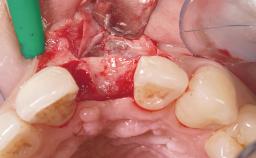

Late Placement of an Implant in a Maxillary Left Central Incisor Site

A 36-year-old female patient was referred for the replacement of the upper left central incisor (tooth 21), which had fractured. Although the tooth had been asymptomatic for many years, the crown began to loosen, at which time she presented to her dentist for an assessment. Teeth 21 and 22 had both been endodontically treated many years previously. She was a healthy individual and a non-smoker.

Soft Tissue Grafting Simultaneous

Abutment Type Customized

Soft Tissue Contour and Volume Slightly compromised